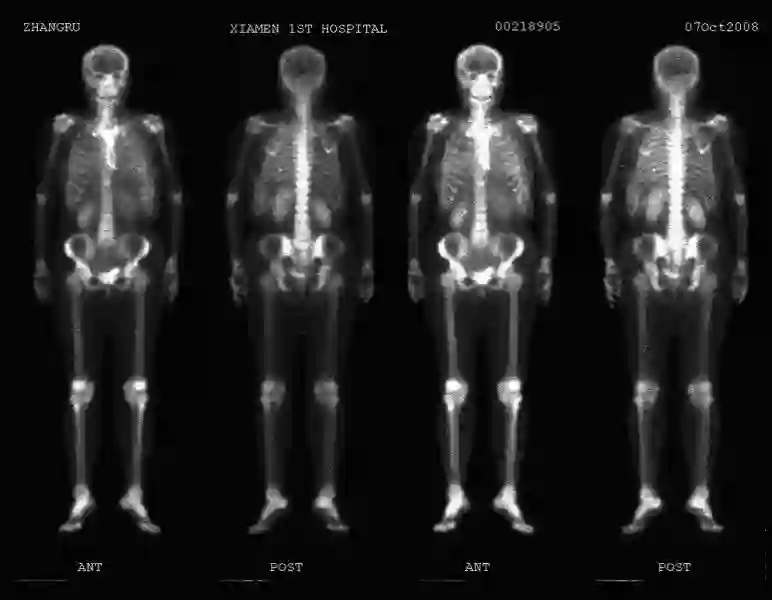

术后1周即开始“紫杉醇+阿霉素”方案术后辅助化疗6周期。2008年2月25日至4月9日在福建某医院行局部放疗25次(DT 5000cGY/25f 三窗),加切口局部放疗6次,放疗后复查ECT全身骨骼无异常发现。

2008年10月7日ECT检查结果